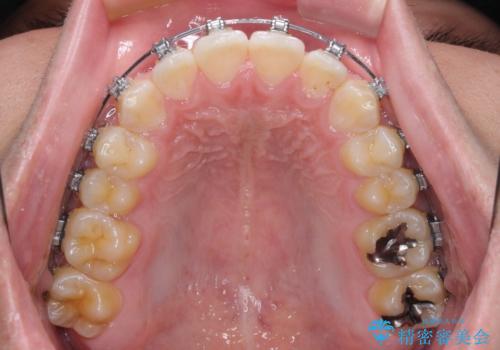

- 矯正装置

- メタルブラケット

- 前歯のデコボコを気にして来院された患者様です。

ワイヤー装置でもマウスピースでも対応可能でしたが、自己管理の煩わしさを気にされ、ワイヤー装置にて矯正治療を行うこととしました。